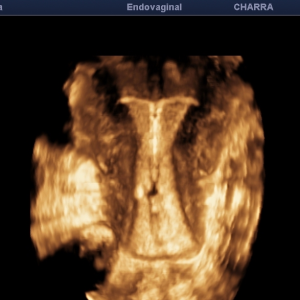

Echographies gynécologiques, Monitorage de l'ovulation (parcours PMA)

Hystérosonographie

Diplômée en Echographie foetale et Gynécologique